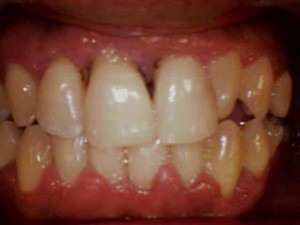

治療前の歯ぐき

歯ぐきが赤く腫れています